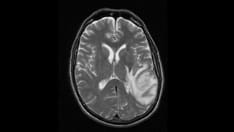

T2-weighted image demonstrates notable edema and midline shift. This finding is consistent with a high grade or malignant tumor. Image courtesy of George Jallo, MD.